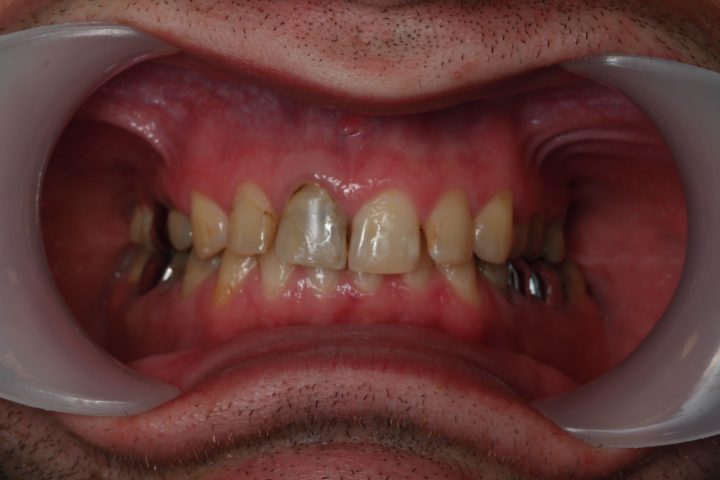

Garreth

Garreth ist ein englischer Synchronisationsschauspieler. Der Zustand seinen Zähnen hat die Lautbildung und seinen Gesundheitszustand schon seit langem gestört.

Wegen seiner Arbeit war die herausnehmbare Prothese ausgeschlossen, weil die Lautbildung und die Sprache sich verändern würden.

Zu gleicher Zeit wurden die obere, zweiseitige Knochenaufbau und die obere Implantation im Kauen Region durchgeführt. Auf beiden Seiten haben wir schweizerische Straumann Implantate, Premium Qualität benutzt.

Er hat unten, in die Kauenregion 2-2 Implantate bekommen. Nach der 6 Monate lange Heilungszeit wurden metallfreie Zirkonkronen auf den Frontzähnen bearbeitet, und auf Implantate Metallkeramik Kronen hergestellt.